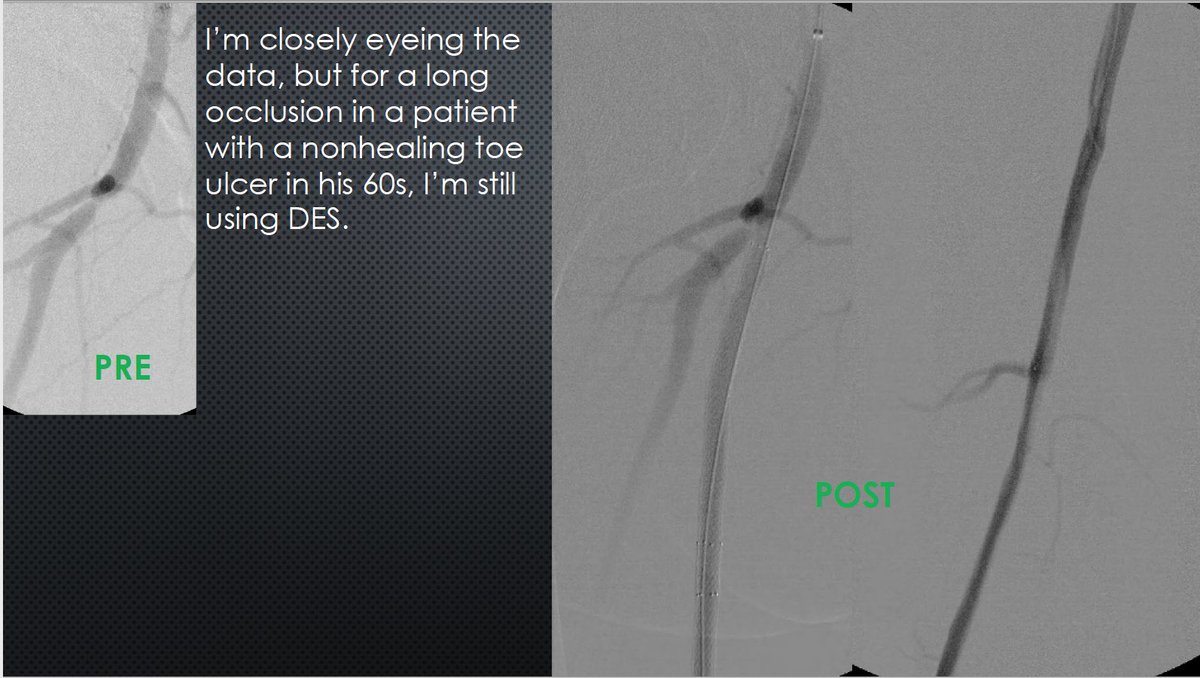

MRA can be MORE sensitive to tibial occlusive disease than DSA. MRA helped plan approach due to knowledge of hibernating AT and peroneal lumen. Successful antegrade luminal recan for #CLI #CLIfighters #mylegmylife @FadiSaab17 @Mustapja @roblookstein @DrBTKatzen @BOlivieriMD